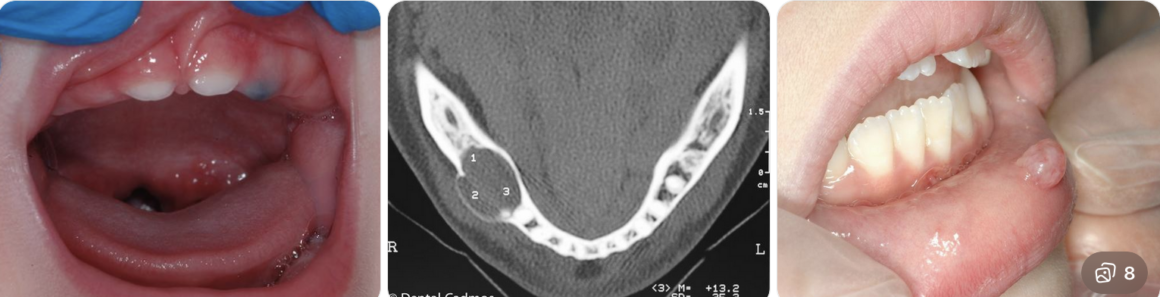

Cisti Orale a Olbia, Sassari

Queste formazioni possono avere origine da infezioni dentali, denti inclusi o traumi, e tendono a crescere lentamente nel tempo.

In molti casi, la cisti viene individuata durante controlli di routine o esami radiografici effettuati presso lo studio RICCARDENT S.R.L.

Con il progredire della patologia possono comparire:

- gonfiore nella zona interessata

- fastidio o dolore

- mobilità dentale

- infezioni locali

Per questo motivo è fondamentale una diagnosi precoce.

Presso RICCARDENT, la diagnosi avviene tramite strumenti avanzati come radiografie digitali e TAC dentale, che permettono di valutare con precisione la posizione e la dimensione della cisti.

Le principali tipologie includono:

- cisti radicolari

- cisti follicolari

- cisti odontogene

Il trattamento consiste generalmente nella rimozione della cisti attraverso interventi minimamente invasivi, eseguiti in totale sicurezza.

Dopo l’intervento, vengono programmati controlli periodici per monitorare la guarigione ed evitare recidive.

Affidarsi a RICCARDENT S.R.L. significa scegliere professionalità, tecnologia e attenzione alla salute orale.

La prevenzione e i controlli regolari restano fondamentali per individuare tempestivamente eventuali problematiche e mantenere un sorriso sano nel tempo.